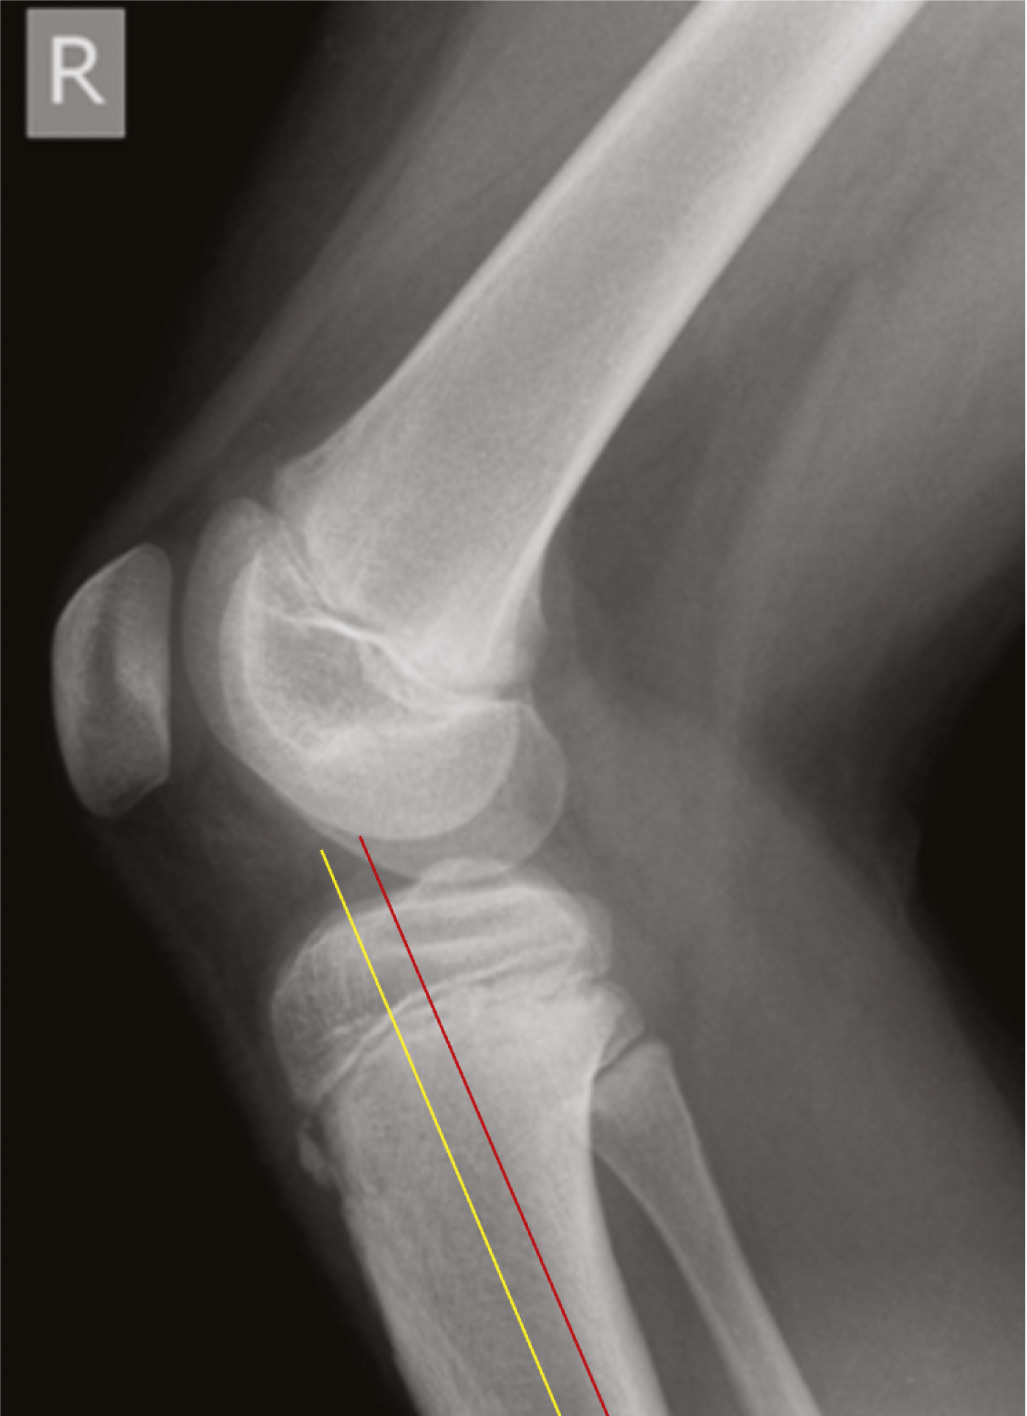

- ~2-3 cm longitudinal incision along approximately the anterior 1/3 of the proximal tibia on lateral XR (see yellow line below). If you were to make the incision at the geometric midpoint of the proximal tibia in the sagittal plane, the posteriorly-flared shape of the proximal tibial metaphysis will cause you to end up too posterior in the diaphysis (see red line below).

- Medial incision: Incise directly over bone (will be near insertion of pes anserinus)

- Lateral incision: Incise through anterior compartment fascia